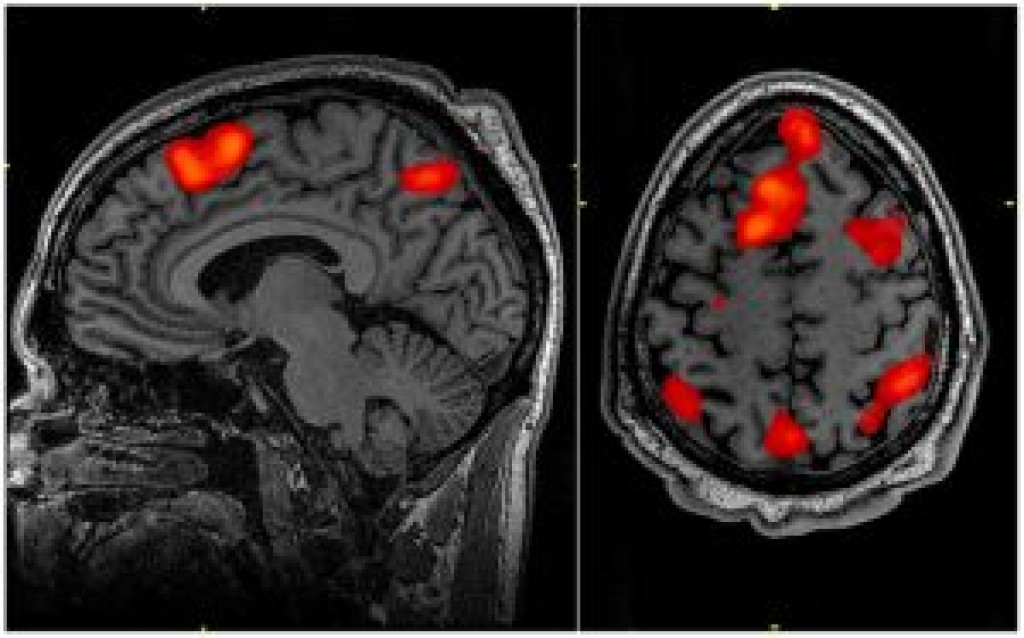

A Doença de Huntington é uma condição hereditária, neurodegenerativa, progressiva, incapacitante e extremamente grave, pertencente ao grupo das doenças raras.

Causada pela perda de células em uma parte do cérebro denominada gânglios da base, ela compromete as capacidades motoras, através de movimentos involuntários dos membros inferiores e superiores.